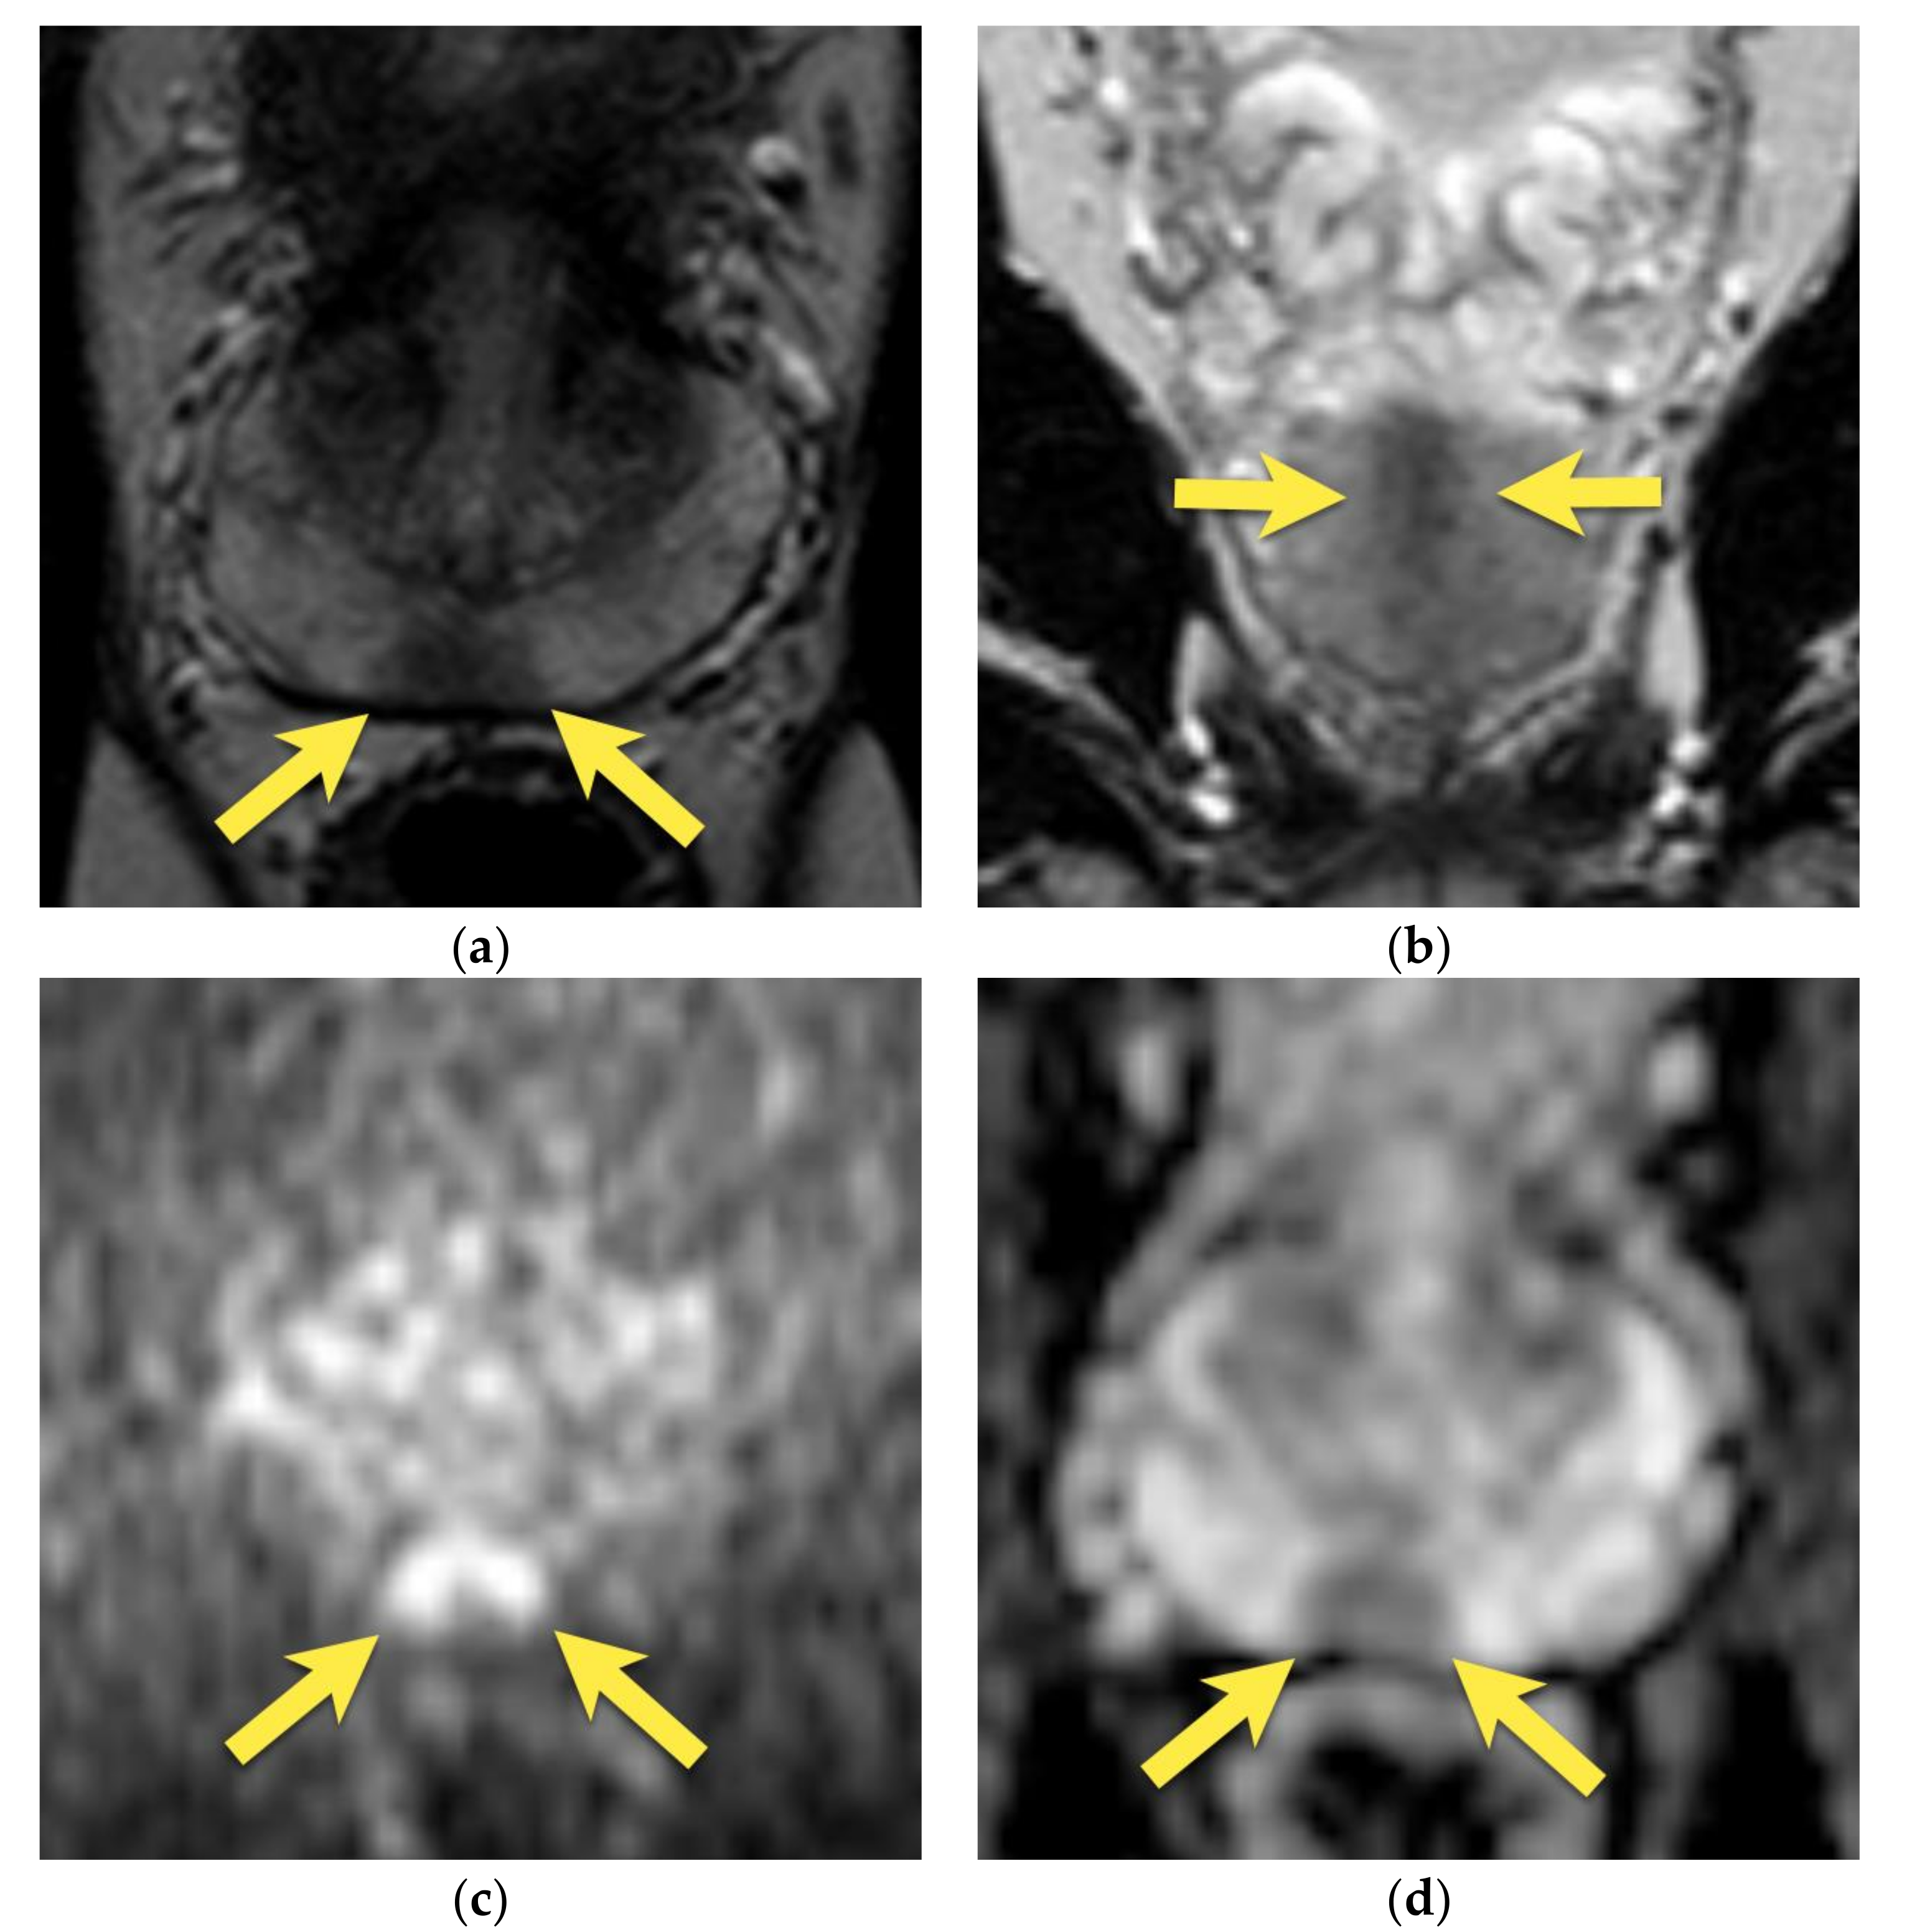

5. Hypointense Area in the Median Posterior Middle Gland or at the Base

8. Post-Biopsy Hemorrhage

9. Prostatitis

10. Prostatic Abscess